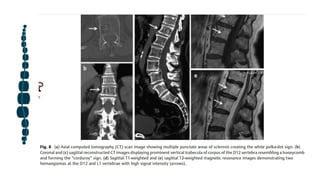

Hemangioma

Los hemangiomas son frecuentes, por lo general se descubren de forma incidental. Lesiones benignas del desarrollo.

Incidencia reportada en autopsia serie es el 11% de las espinas, y las lesiones multifocales están presentes en 25 al 30%

de los casos.

Las lesiones ocurren con mayor frecuencia en columna torácica, pero puede estar presente en cualquier nivel de la

columna.28 Los hemangiomas revelan trabéculas verticales prominentes en las radiografías que se asemejan a un "panal"

y clásicamente llamadas "Letrero de pana".

Forman la apariencia de múltiples áreas puntuales de esclerosis en las imágenes de TC axiales, creando el "blanco signo

de lunares ”. El estroma graso y los canales vasculares serpentinos son responsables de los componentes de baja

densidad en la llanura. radiografías e imágenes de TC.

El crecimiento excesivo de grasa exhibe señal paralela al tejido adiposo subcutáneo, y los

componentes vasculares demuestran una alta intensidad de señal en un patrón serpentino en

la RM ponderada en T2 que refleja flujo sanguíneo lento. La apariencia de lunares o pana

puede también se puede ver, respectivamente, en RM axial y sagital / coronal imágenes como

regiones de baja intensidad de señal

Hemangiomas con extensión a los elementos posteriores, con afectación paravertebral y sin

gran cantidad de estroma graso intertrabecular, es más probable que estén asociados con

síntomas.

Lesiones que contienen menos grasa y más vasculares. estroma tienden a ser menos comunes,

y se encuentran entre T3 y T9. Grandes hemangiomas que debilitan la vertebral los cuerpos

pueden resultar en fracturas. Fractura patológica o epidural la extensión puede mostrar un

"signo de cortina" característico.

Una lesión del cuerpo vertebral que se extiende posteriormente a la epidural anterior. el

espacio desplaza el ligamento longitudinal posterior